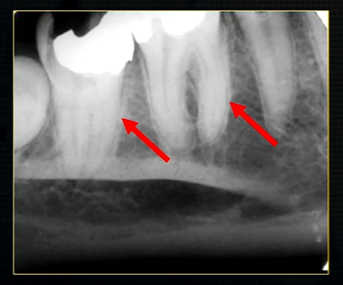

periapical radiograph → posterior maxilla

radiolucent maxillary sinus and radiopaque floor

radiopaque shadow cast by zygoma, hollowed out by maxillary sinus

lower end of the dense, zygomatic bone

posterior aspect of the maxilla - smooth round tuberosity